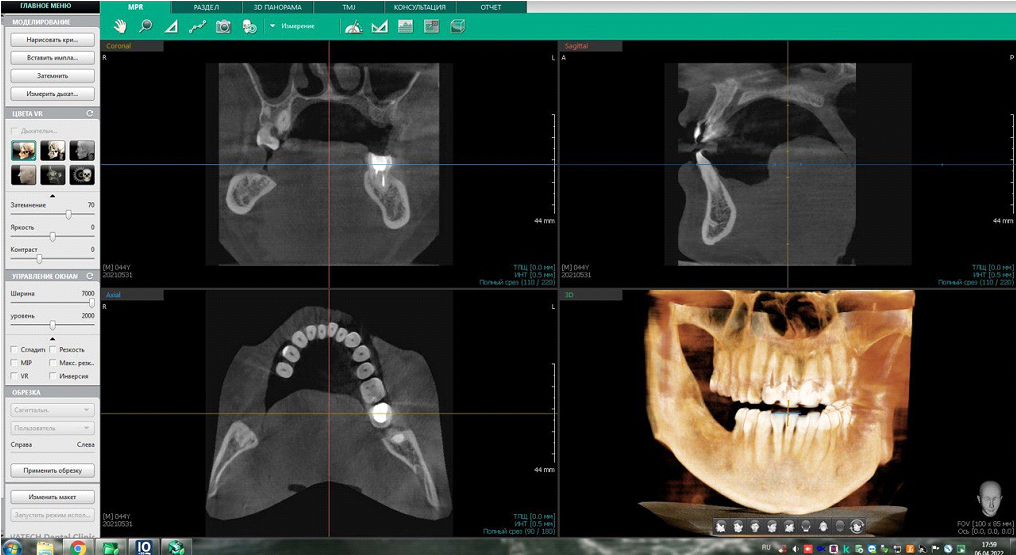

Можно приложить модель импланта к снимку. В просмотрщике у нас есть линейка, чтобы сразу замерять объекты на проекциях. Также мы можем импортировать всё это в проектировочное ПО и накладывать разные модели имплантов, например, прямо на снимок. Туда же можно добавить панорамное сканирование ротовой челюсти и получить максимальную детализацию для навигационных шаблонов будущей операции.

То есть мы видим красивую картинку 3D-модели и срезы, в которых можем двигать точку зрения. Врачи обычно работают именно со срезами, 3D-модель нужна для продажи ПО на выставках.